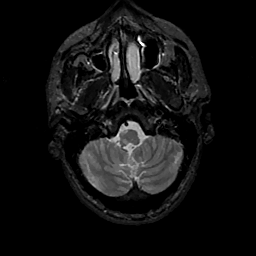

MR Study #11, May 5, 1991 -- Slice #7